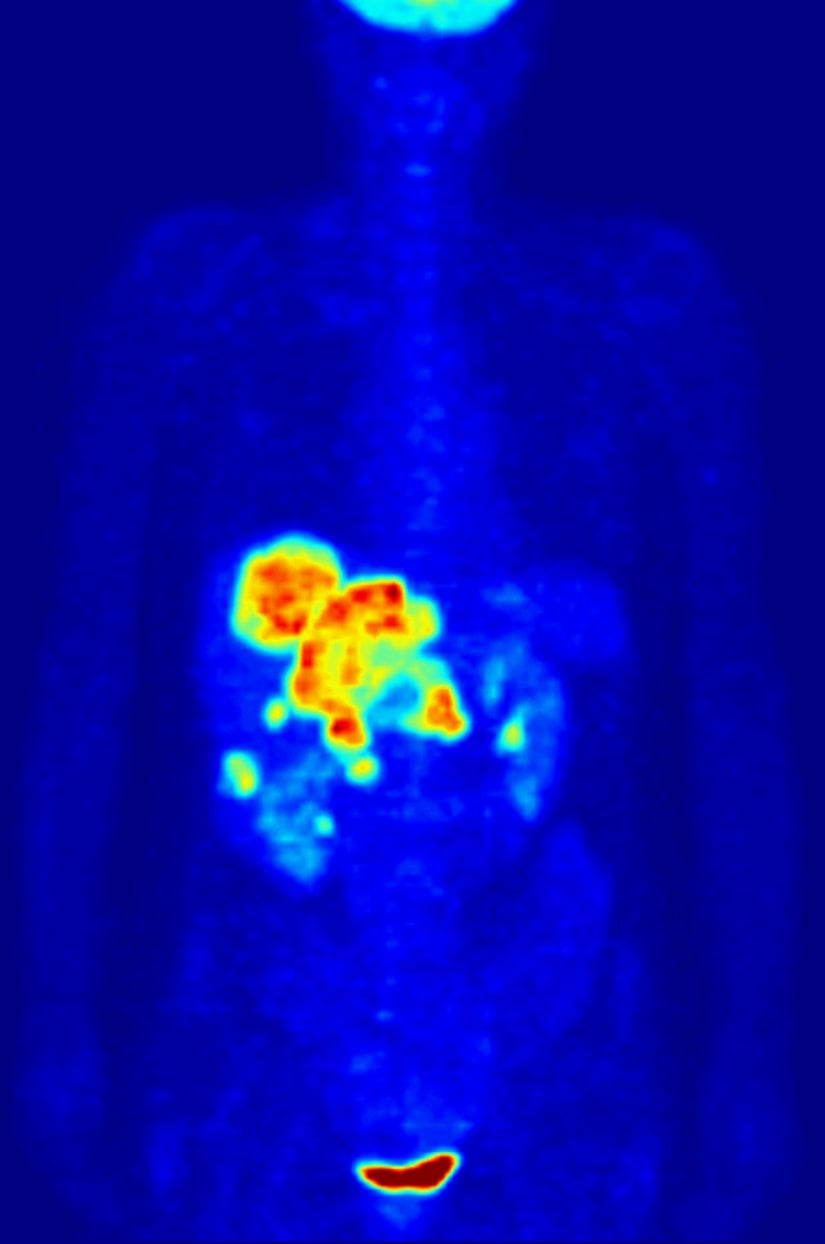

Kanser

Kanser hücreleri, normal hücrelere göre daha yüksek metabolik aktiviteler gösterir. İşleyişlerindeki bu farklılıktan dolayı kanserli dokular, PET taramalarında parlak bölgeler halinde görünür. Bu sayede PET taraması kanser teşhisi dışında şu amaçlara da hizmet eder:

- Kanserin yayılımının izlenmesi

- Kanser tedavisinin etkinliğinin ölçümü

- Tekrarlamış kanserlerin tespiti

Yine de tarama sonuçları doktor tarafından dikkatli incelenmelidir; çünkü taramada, bazı kanser olmayan olaylar kanser gibi görünebilir. Ayrıca, PET taramalarında solid tümörlerin görüntülenmesi başarısız olabilir.